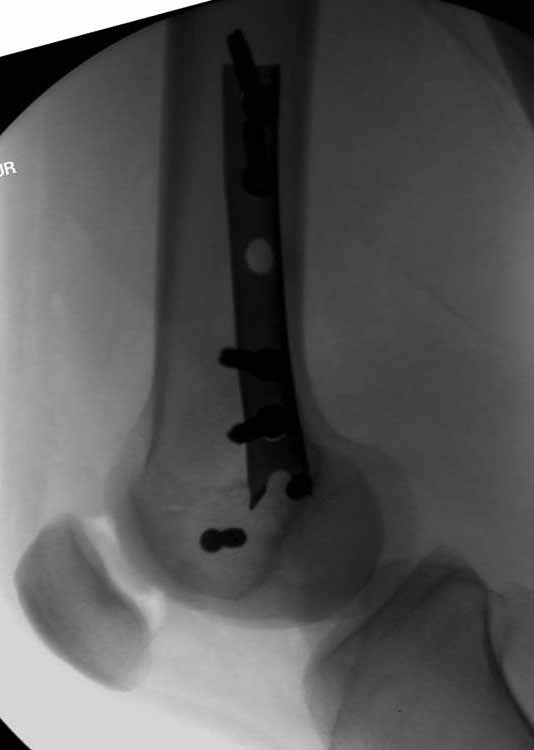

Ну зачем же так. Всё-таки считается "золотым стандартом". Во вложенном файле коллаж из сохранившихся фотографий одной из операций. Всё сделано закрыто и без ЭОПа.

Ответ на эту часть Вашего поста – вложенный файл. Больная оперирована неделю назад по поводу открытого перелома дистального эпиметафиза бедренной кости. После операции она идёт в рентгенкабинет для выполнения послеоперационной контрольной рентгенографии, представленной на слайдах 10 и 11. Узнав, почему её фотографируют, просила передать Вам, Антон, привет.